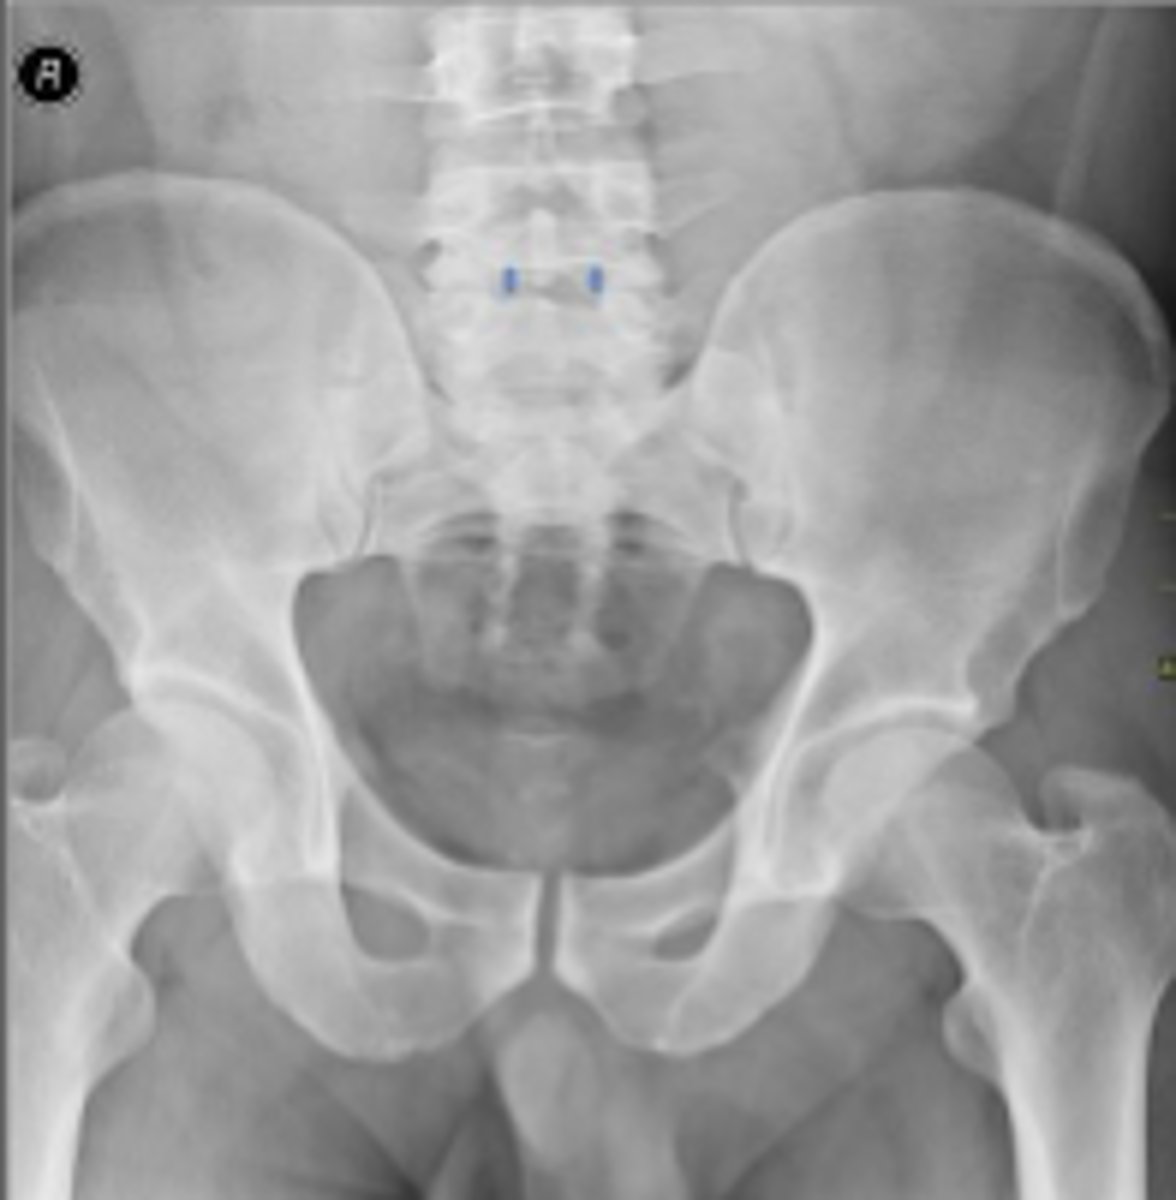

Bilateral frog leg view

What is the name of the radiographic view?

Left and right posterior inferior iliac spine

What are the arrows pointing to?

Posterior rim of the left acetabulum